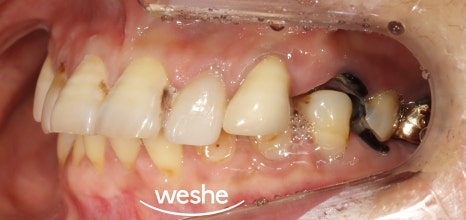

먼저, 엑스레이와 구강 내 모습을 보며

검진을 진행합니다.

예시 사진에서는

치주 질환과 충치로 인해 잇몸뼈가 내려앉거나

치아머리가 사라져 있는 것을

확인할 수 있습니다.

이러한 문제는

자연치의 기능을 하지 못하기에

발치 후 임플란트 를 하는 것이

하나의 방법입니다.